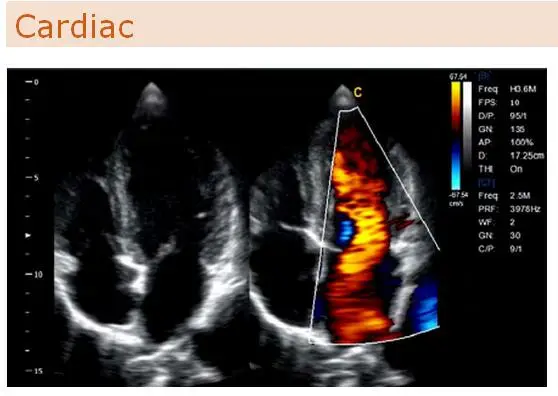

Color flow (CF), Power Doppler (PDI), Directional Power Doppler (DPDI)

B+CF color double-frame real-time imaging

Electronic phased array

Scanning Images